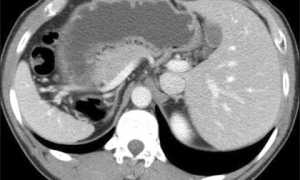

Исследование брюшной полости и забрюшинного пространства требует тщательной подготовки пациента. Наличие пищевых остатков и газов может значительно исказить результаты. Поэтому рекомендуется проводить КТ натощак, иногда с предварительным приемом спазмолитиков. Особое внимание уделяется оценке состояния паренхиматозных органов, таких как печень, почки и поджелудочная железа. Этот метод позволяет обнаруживать очаговые изменения размером от 2-3 мм, что крайне важно для ранней диагностики онкологических заболеваний.

| Брюшная полость | Печень, желчный пузырь, поджелудочная железа, селезенка, почки, надпочечники, кишечник, крупные сосуды | Опухоли, кисты, камни, воспалительные процессы (панкреатит, холецистит), травмы, кровотечения, аппендицит |